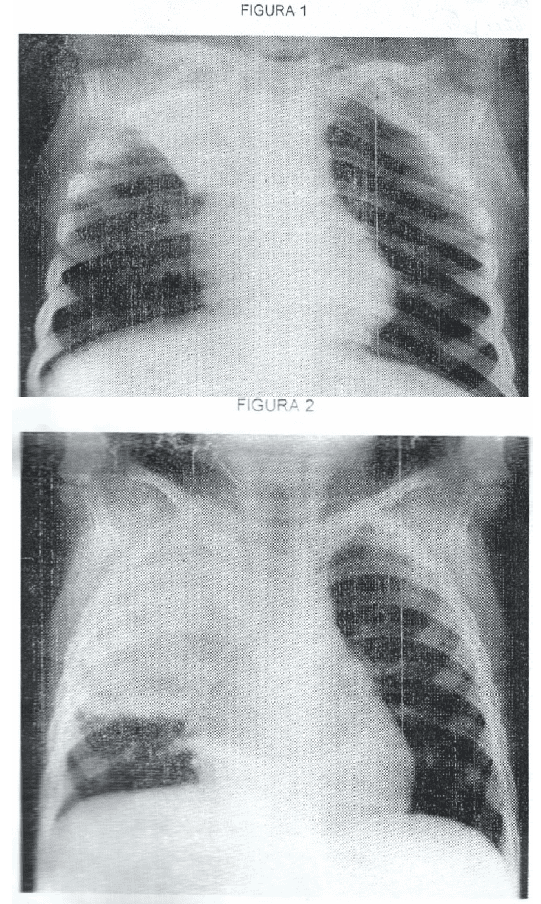

54)En la imagen radiológica de la figura 1 (ver Anexo) observamos:

a) Una imagen de condensación pulmonar que no respeta límites anatómicos.

b) Una imagen que aumenta el volumen del lóbulo o segmento condensado.

c) Un desplazamiento del mediastino hacia el lado opuesto de la condensación.

d) Retracción de las cisuras y del hemidiafragma hacia la imagen de

condensación.

63)En la imagen radiológica de la figura 2 (ver anexo) observamos:

a) Imagen de condensación pulmonar que respeta límites anatómicos.

b) Imagen de hiperaereación pulmonar que disminuye el volumen pulmonar.

c) Imagen micronodular pulmonar bilateral.

d) Imagen de opacificación pulmonar con nivel hidroaéreo.